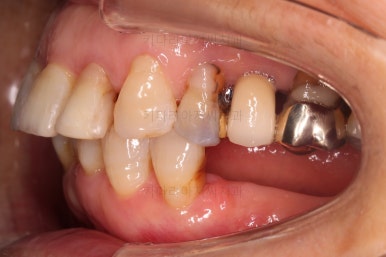

초진 시 입안의 모습입니다.

일반적인 교정을 하기에는 적합한 모습은 아니었어요.

치아는 군데군데 없고 임플란트도 있고 브릿지로 연결된 치아도 있으며 전반적인 잇몸 상태도 좋지 못했어요.

앞니가 벌어져 있고 뻗쳐 있으며 잇몸에서 쏙 빠져나와 있는 듯한 느낌이었어요.